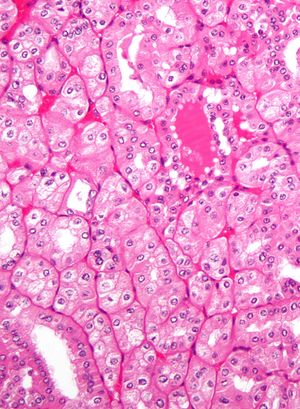

| Micrograph showing the most common type of kidney cancer (clear cell renal cell carcinoma). H&E stain. | |

The most common type of kidney malignancy is renal cell carcinoma,[11] which is thought to originate from cells in the proximal convoluted tubule of the nephron.[9][12] Another type of kidney cancer although less common, is transitional cell cancer (TCC) or urothelial carcinoma of the renal pelvis.[13] The renal pelvis is the part of the kidney that collects urine and drains it into a tube called the ureter.[13] The cells that line the renal pelvis are called transitional cells, and are also sometimes called urothelial cells. The transitional/urothelial cells in the renal pelvis are the same type of cells that line the ureter and bladder. For this reason TCC of the renal pelvis is distinct from RCC and is thought to behave more like bladder cancer.[13] Other rare types of kidney cancers that can arise from the urothelial cells of the renal pelvis are squamous cell carcinoma and adenocarcinoma.[9]